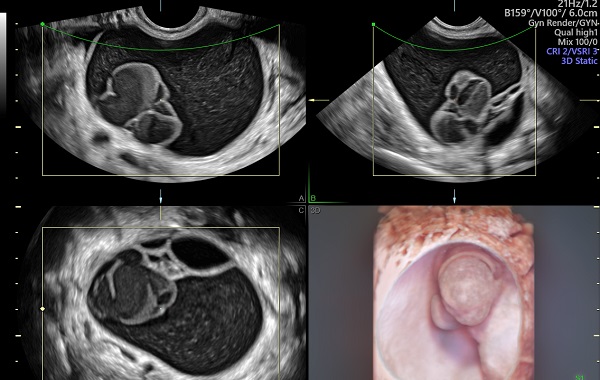

- Siêu âm

Siêu âm chẩn đoán u nang buồng trứng